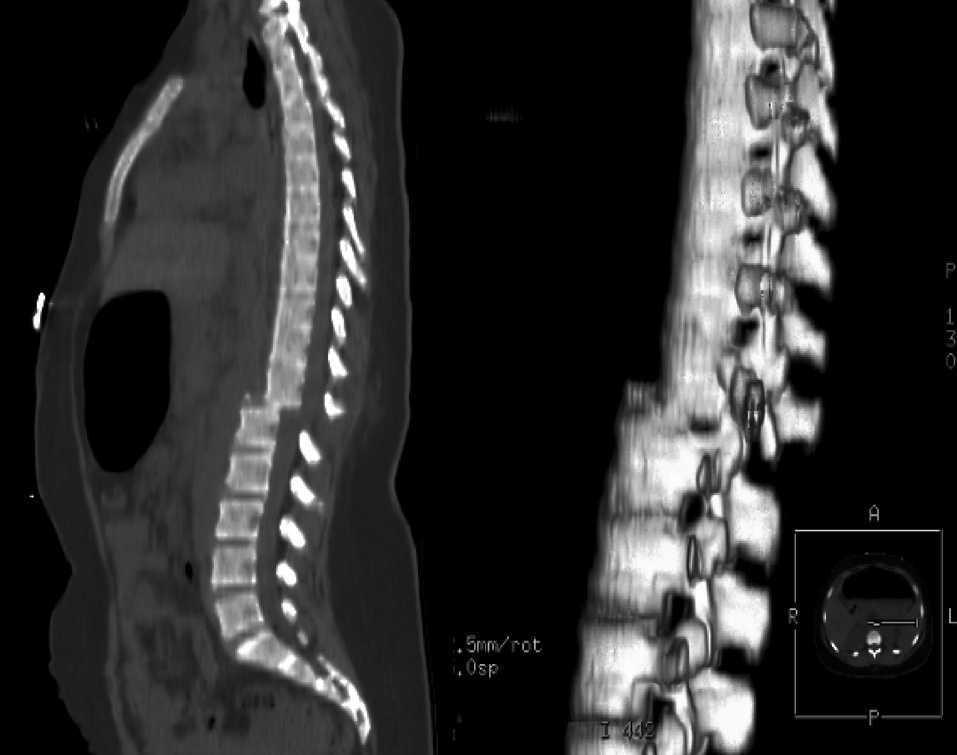

Tiempo a la descompresión y resultados funcionales en la lesión espinal aguda

La descompresión quirúrgica dentro de las 24 horas posteriores a la lesión medular aguda se asocia con una mejor recuperación sensoriomotora. The Lancet Neurology, 21 de diciembre de 2020.